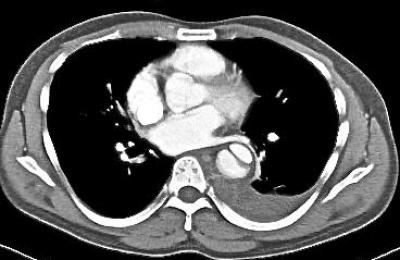

Figure 1a: Contrast enhanced CT angiogram of the thorax reveals an intimal flap within the descending aorta giving rise to a true and false lumen.